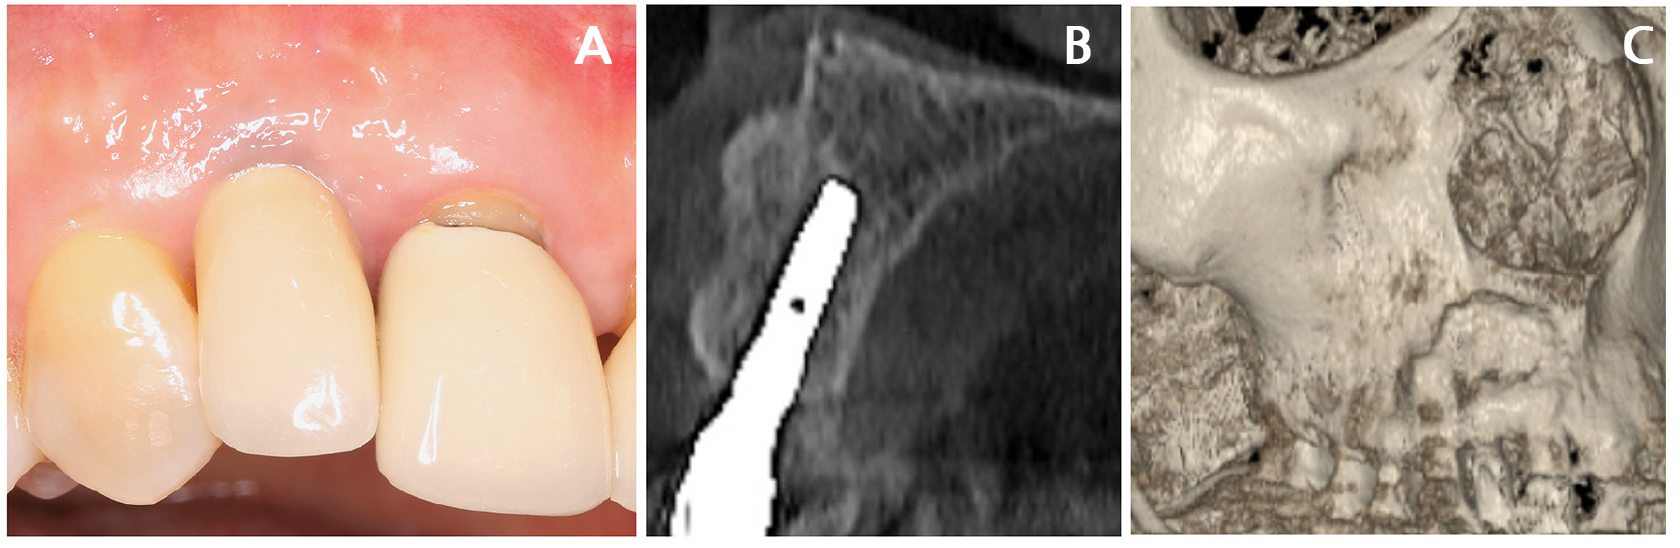

A 42-year-old non-smoking female visited a private clinic for implant treatment of a missing right maxillary lateral incisor. Panoramic and cone-beam computed tomography (CBCT) revealed an atrophic bone plate at the #12 site (Fig. 1A and 1B). The tooth was extracted 1 year prior. Lateral bone augmentation was scheduled simultaneously with the implant placement.

The patient was regularly followed up. On clinical examination at 4 years of age, healthy peri-implant tissue was observed. CBCT examinations at that time exhibited well-consolidated augmented bone, with relatively decreased radiopacity at the mid-portion of the augmented area compared to the coronal and apical surfaces. In the reconstructed three-dimensional image, a small irregular depression was observed at the apical region of the augmentation (Fig. 2). However, no further abnormalities were observed.

A 7-years post-implantation, the patient reported slight tenderness in the labial mucosa at the implant site. Mucosal recession (approximately 1 mm) developed in the labial area, and the metal collar was slightly exposed. The probing depth was less than 3 mm, with bleeding on probing noted in the midfacial area. On CBCT examination, depression of the facial contour of the augmented bone and further loss of radiopacity were observed. The reconstructed three-dimensional image demonstrated progression of the previously noted depression (observed at 4-years of follow-up). Compared to the clinical photographs taken at the time of surgery revealed that the site of depression corresponded to one of the intramarrow penetration holes (Fig. 2).

Fig. 2

Clinical and radiographic characteristics during recall visits. (A, B, C) Clinical conditions, (A) immediately following final prosthesis delivery, (B) at 4 years, (C) at 7 years, (D, E, F) coronal sections of the cone-beam computed tomography (CBCT) scans, (D) immediately after final prosthesis delivery, (E) at 4 years, (F) at 7 years. (G, H, I) Three-dimensional reconstruction of the CBCT images, (G) immediately after final prosthesis delivery, (H) at 4 years, and (I) at 7 years. The arrows indicate bone depression in the reconstructed images.